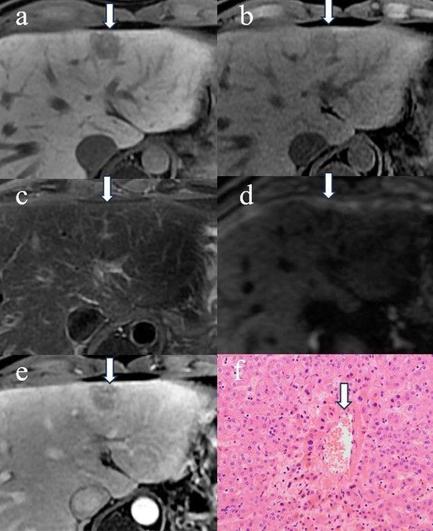

A study on gadoxetic acid-enhanced MRI of benign hepatic lesions following chemotherapy showed distinctive imaging features. Early-term lesions often resolved spontaneously, while late-term FNH-like lesions may grow in size and number. (Yiqi Wang et al.)